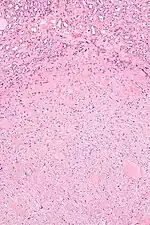

| Micrograph of a renal medullary fibroma (bottom of image). Renal tubules are seen at the top of the image. H&E stain. | |

They consist of bland spindle-shaped or stellate-shaped cells in a loose stroma. Renal tubules may be entrapped.

Low mag.